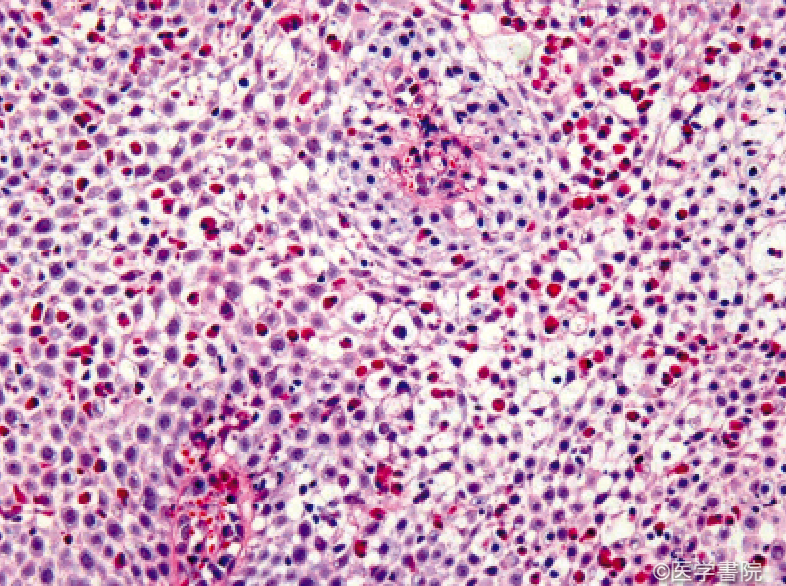

好酸球性食道炎を確定診断する唯一の方法は内視鏡検査です。

この手術では、胃腸科医が鎮静下にカメラを備えた細いチューブを食道に挿入します。医師は組織の生検材料を収集し、好酸球の検査のために病理学者に送ります。

病理学者から生検結果が返されたら、医師は好酸球性食道炎が症状の原因であるかどうかを判断できます。